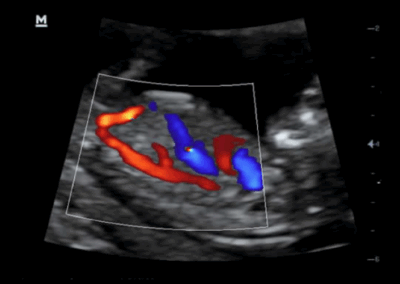

Z50

Sistema de diagnóstico ecográfico.

Con la combinación definitiva de alto rendimiento, aplicaciones clínicas integrales y diseño integrado, el Z50 lo ayudará a responder de manera más rápida y eficaz. El cambio de un sistema en blanco y negro a un sistema Doppler a color altamente eficiente ahora se ha vuelto más fácil y simple que nunca, lo que hace posible ir más allá de los límites y trascender lo habitual cuando se trata de la atención de los pacientes.